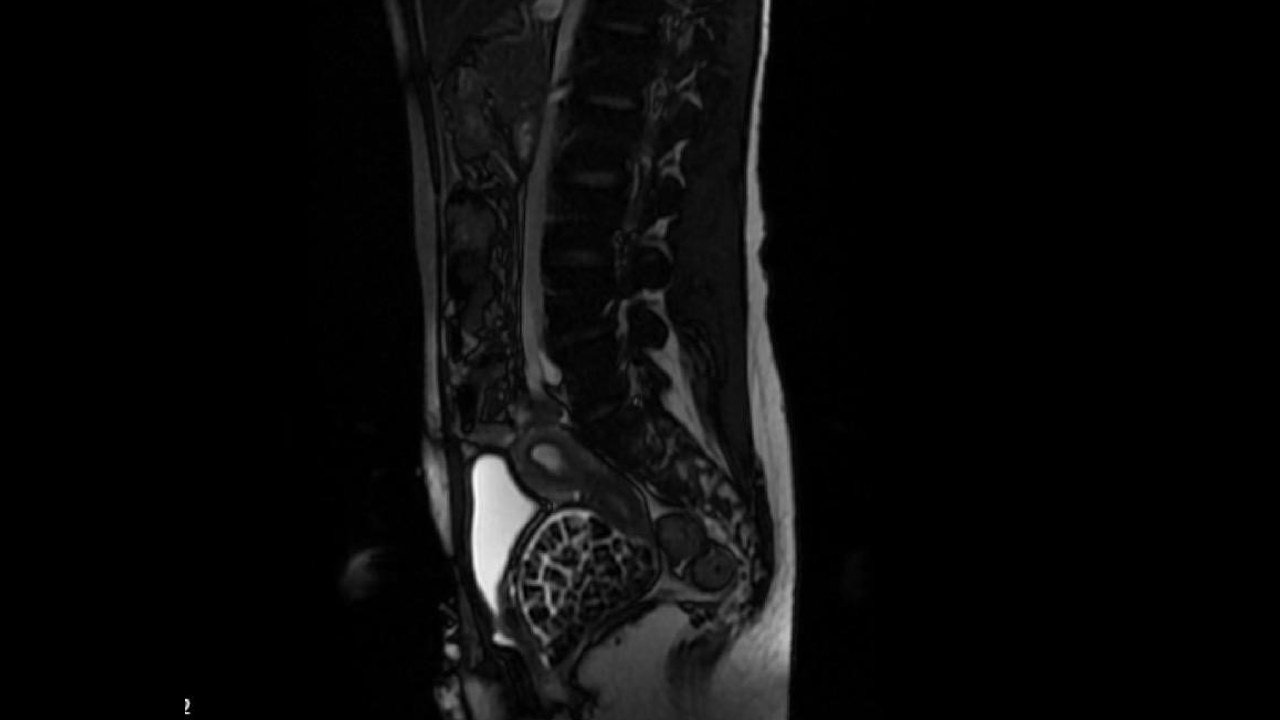

"287 adet taş çıkardık, literatürde çok nadir görülen bir olay" Hastasının durumuna yönelik konuşan Üroloji Uzmanı Doç. Dr. Erkan Erkan, "Hastamızın 2004 yılında doğduğunu ardından doğar doğmaz ekstrofi vezika dediğimiz 50 binde bir görülen bir anomaliden dolayı art arda ameliyatlar geçirdiğini öğrendik. 10 yaşında yine bir ameliyat geçirmişti, gerekli görüntüleme ve tetkiklerimizi yaptırdık. Normalde mesanesinin olması gereken yerin hemen arka kısmında taşlarla dolu bir kese olduğunu gördük, bunun üzerine ek görüntülemeler; MR çektirdik. Hastamız çelişkili açıklamalar almıştı, kendi radyolojik kliniğimiz ve edindiğimiz konsültasyonlarda taşların mesanede değil vajinal boşlukta oluştuğunu düşündük, bir planlama yaptık. Kadın doğum hocamızın da çabasıyla taşları tamamen temizledik ardından ileride normal bir hayat sürmesi bakımından oraya plastik cerrahi yaptık. 287 adet taş çıkardık, pratikte gerçekten görünce çok şaşırdık çünkü bu aynı zamanda literatürde çok nadir görülen bir olay. Biz ameliyata hazırlanırken de teorik olarak biraz araştırdık. Literatürde gördüğümüz kadarıyla buna benzer bu tanıma uyan bir vaka vardı. Literatürde sanırım yayınlanmış 2’nci vaka olacak. Farkındalık çok önemli, bilinçli bir hastamız vardı. Doğumsal anomaliyle doğan çocuklarımızda ileride bunlara bağlı bazı sıkıntılar çıkabileceğinin öngörülmesi lazım. İlgili tedavilerini alsalar bile düzenli takiplere gelmeleri gerekiyor. İleride eğer dikkat etmezse ki zannetmiyorum, tekrarlayabilir. Bu rahatsızlık ekstrofi vezikal epispadias durumu çok nadir bir durum" dedi.

"Tüm vajenin taşlarla dolu olduğunu gördük" Genç kızın uzun süredir devam eden karın ağrısı olduğunu söyleyerek sözlerine başlayan Jinekolojik Onkoloji Uzmanı Op. Dr. Emin Erhan Dönmez, "Mesane taşları olduğu düşünülerek daha büyük bir hastaneye refere edilmiş. Aramızda mini bir konsey yaparak muayene ettik. Vajen bir hazne görevi görerek orada durağan bir idrar, uzun süre beklediği için idrar içindeki minerallerde çökerek taşlar oluşmuş. Mesanedeki idrarın vajene akmış olabileceği ve vajende göllenen idrar nedeniyle taşların burada oluşacağını düşündük, ameliyatımızı planladık. Ameliyata tanı amaçlı girmiştik, sistoskopi (Mesane gibi idrar yollarını kapsayan kısımlardaki rahatsızlıkların teşhis ve tedavisinde kullanılan endoskopik bir yöntem) dediğimiz ameliyatı Erkan Hocam ile birlikte gerçekleştirdik. Önce mesaneyi bir görüntüledik, mesane tabanına yaklaşık 2-3 cm’lik bir alandan vajene fistülize olduğunu gördük. Mesaneden vajene geçtiğimiz esnada tüm vajenin taşlarla dolu olduğunu gördük.

Tanı amacıyla girdiğimiz ameliyatta her şey de olağan gittiği için tedaviye geçtik. Taşların çıkabileceği kadar bir genişlik sağladık. Daha sonra yaklaşık en büyüğü 2,5 cm boyutlarında olan, irili ufaklı 287 tane taşı ameliyat esnasında çıkarmış olduk. Taşların tekrarlamaması için idrarın göllenmemesi, en azından dışarıya rahatça boşalabilmesi için vajinal rekonstrüksiyonu sağladık. Ameliyatta da herhangi bir problem yaşamadık. Literatürü Erkan Hocam ile birlikte değerlendirmiştik. Primer olarak vajende birikmiş olan bu kadar çok sayıda taşla ilgili bir makale görmedik, rastlamadık" dedi.